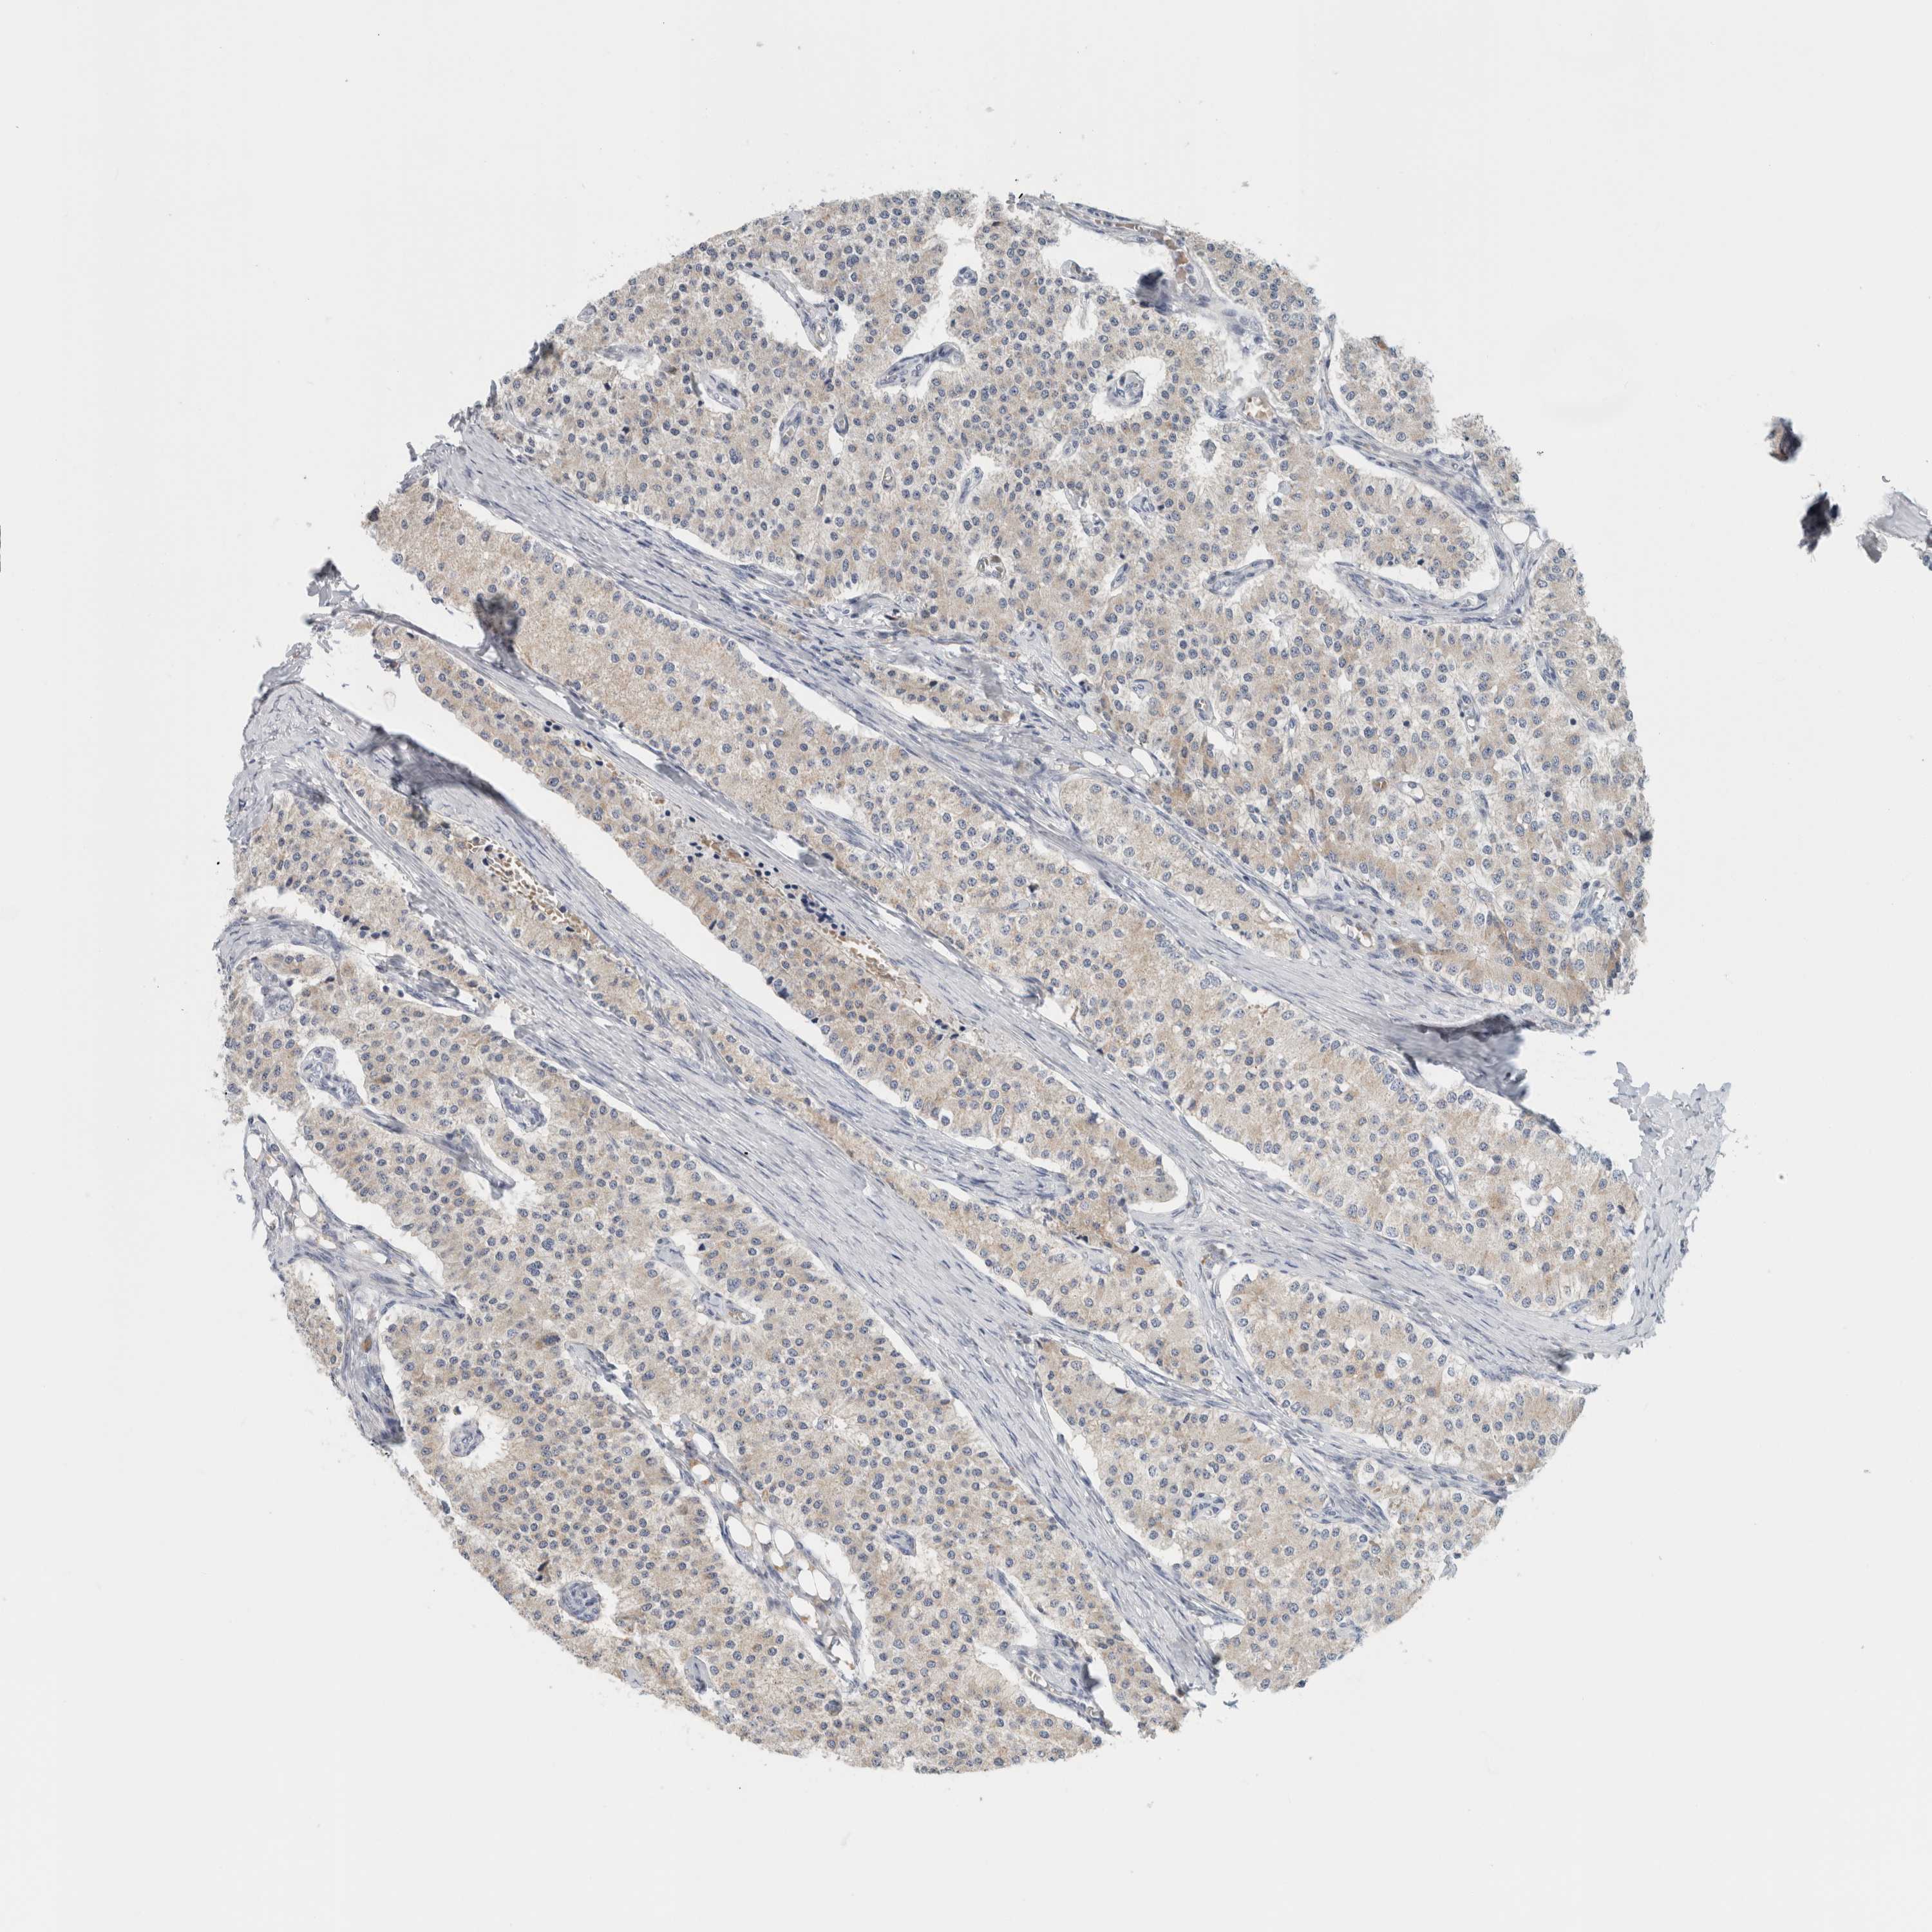

CARCINOID - Protein expressioni

A mouse-over function shows sample information and annotation data. Click on an image to view it in a full screen mode. Samples can be filtered based on level of antibody staining by selecting one or several of the following categories: high, medium, low and not detected. The assay and annotation is described here.

Antibody staining in the annotated cell types in the current human tissue is reported as not detected, low, medium, or high, based on conventional immunohistochemistry profiling in selected tissues. This score is based on the combination of the staining intensity and fraction of stained cells.

Each image is clickable and will lead to virtual microscopy that enables deeper exploration of all samples and also displays staining intensity scores, fraction scores and subcellular localization as well as patient and tissue information for each sample.

Antibody HPA022815

Staining

High

Medium

Low

Not detected

Intensity

Strong

Moderate

Weak

Negative

Quantity

>75%

75%-25%

<25%

None

Location

Nuclear

Cytoplasmic/membranous

Cytoplasmic/membranous,nuclear

Carcinoid, malignant, NOS

Carcinoma, NOS